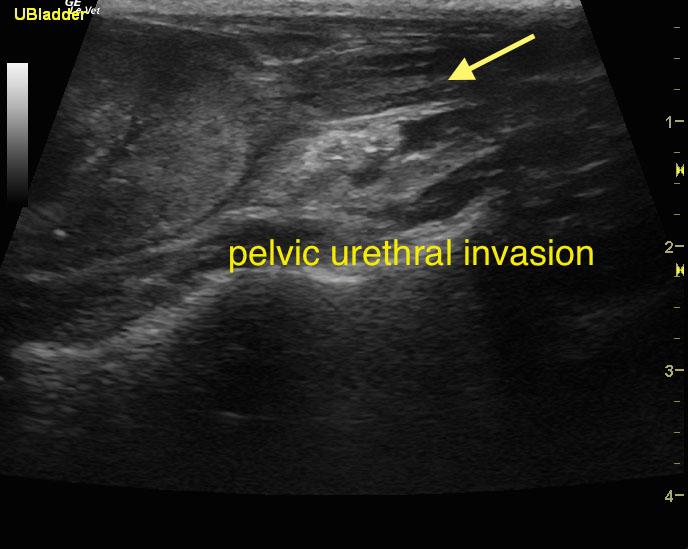

An 18-year-old SF DSH was presented for evaluation of hematuria and stranguria. Urinalysis showed SG of 1.019 and proteinuria. Abnormalities on CBC and serum biochemistry were anemia and azotemia.

An 18-year-old SF DSH was presented for evaluation of hematuria and stranguria. Urinalysis showed SG of 1.019 and proteinuria. Abnormalities on CBC and serum biochemistry were anemia and azotemia.